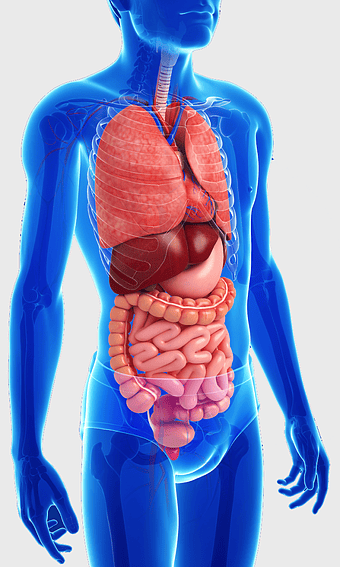

human gastrointestinal tract anatomy, human digestive system illustration, gastrointestinal disease symptoms, human body organ diagram, internal organ visualization, medical anatomy study, digestive health awareness -

human anatomy illustration, male body diagram, human limb structure, surface anatomy chart, human skeletal outline, full-body medical sketch, human joint depiction -

human anatomy illustration, family medicine clinic visuals, blood pressure monitoring, shoulder and hip anatomy, medical diagram of human body, circulatory system depiction, health clinic -

human internal organs illustration, heart and lung anatomy, kidney and liver diagram, brain and stomach structure, medical organ chart, human body systems visual, educational anatomy graphics -